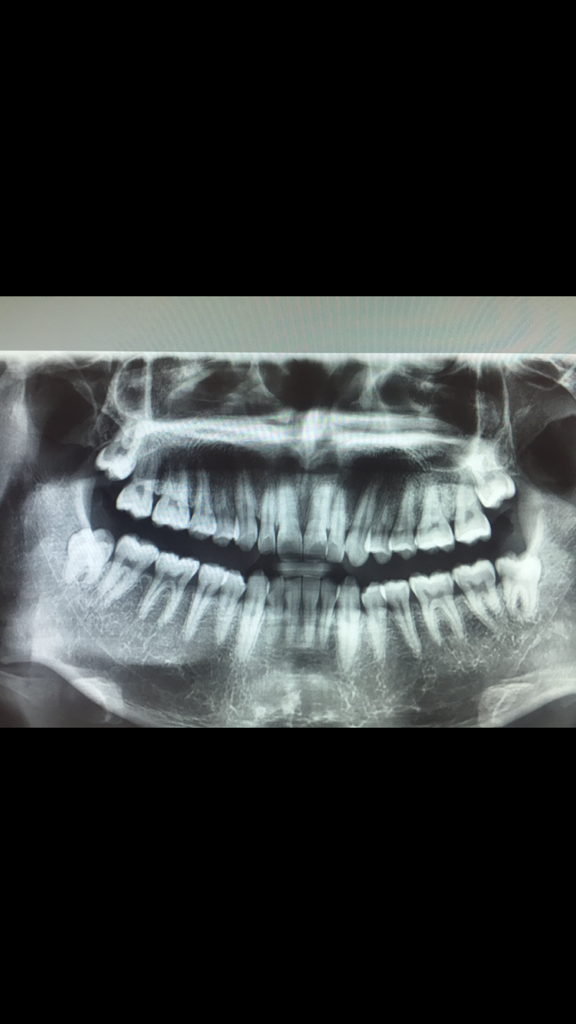

사랑니 사진상 하악 각각 난이도 각각 어떤가요 ??

• 1번 째 사진

현재 사진상으로 각도가 많이 기울어져 있지 않기에 크게 어려운 사랑니 발치는 아닙니다. 발치후 1-2주정도는 흡연및 음주는 피해야하며, 15일 경과시에는 크게 문제가 되지 않습니다.

상악의 사랑니는 쉽게 나올 수 있는 형태로 보입니다. 하지만 하악의 경우에는 완전히 맹출된 것이 아니고 하악 치조골 뒤에 부분이 걸려 있기 때문에 잇몸을 열거나 치조골을 다듬고 발치를 해야 할 수 있습니다.

이런 경우에는 수술의 범위가 넓어질 수 있기 때문에 불편감을 클 수 있습니다.

사진상 상악 사랑니 2개는 locking되는 부분이 없고 더 맹출이 가능합니다. 좀 더 내려왔을 때 빼줘도 되고 관리를 잘해서 충치가 안생긴다면 굳이 뽑지 않아도 될 정도의 맹출 각도입니다.

아래 사랑니의 경우 둘다 부분매복이어서 경우에 따라 발치 중 부분적으로 뼈를 삭제하고 할 수도 있습니다.